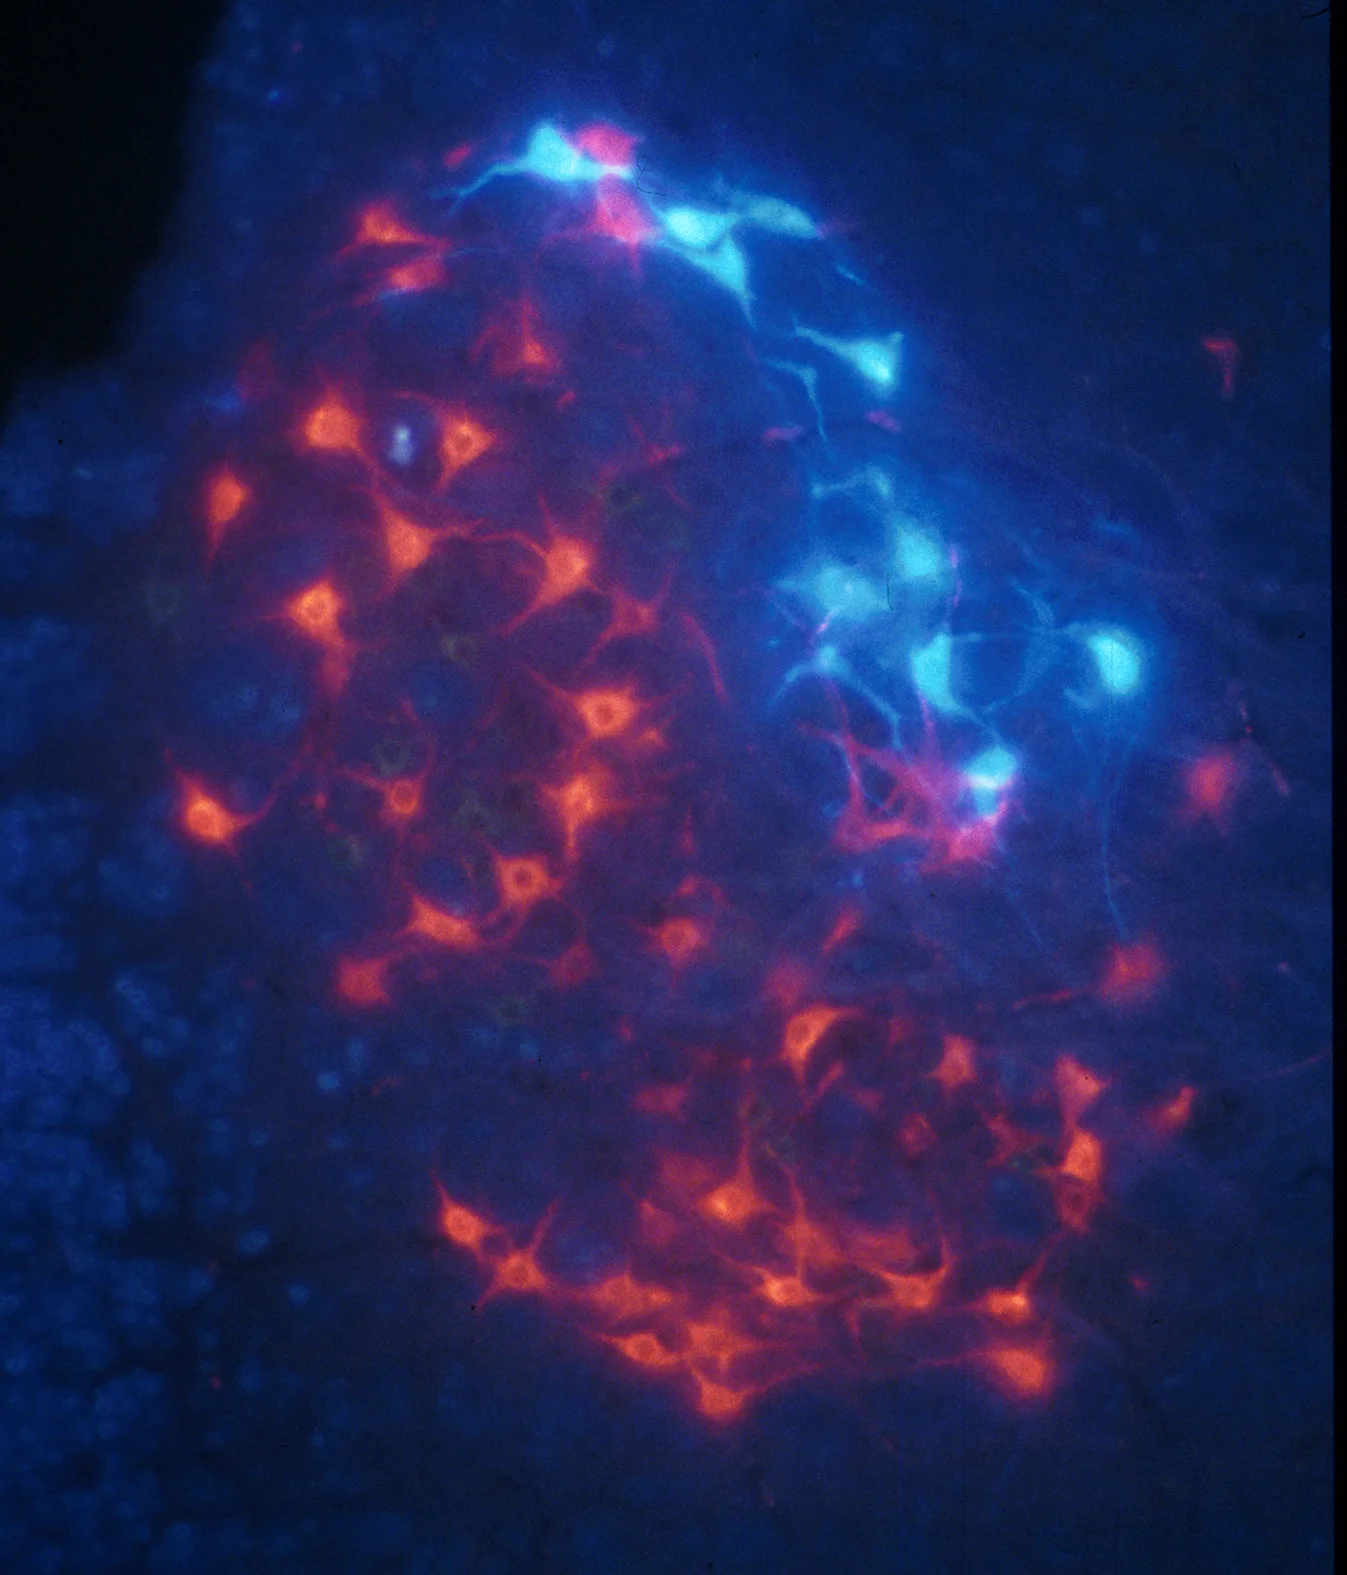

Nerve repair

Spinal Injury, Brachial plexus injury

Cellular therapies

Olfactory ensheathing cells, Good Manufacturing Practice